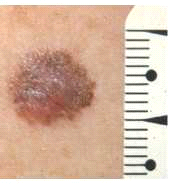

| 16:50, 11 באוגוסט 2014 | Melanoma-06.png (קובץ) |  |

119 קילו־בייטים | Motyk | 1 | |

| 10:07, 11 באוגוסט 2014 | Melanoma-05.png (קובץ) |  |

26 קילו־בייטים | Motyk | 1 | |

| 10:07, 11 באוגוסט 2014 | Melanoma-04.png (קובץ) |  |

23 קילו־בייטים | Motyk | 1 | |

| 10:07, 11 באוגוסט 2014 | Melanoma-03.png (קובץ) |  |

26 קילו־בייטים | Motyk | 1 | |

| 10:06, 11 באוגוסט 2014 | Melanoma-02.png (קובץ) |  |

24 קילו־בייטים | Motyk | 1 | |

| 10:06, 11 באוגוסט 2014 | Melanoma-01.png (קובץ) |  |

21 קילו־בייטים | Motyk | 1 | |